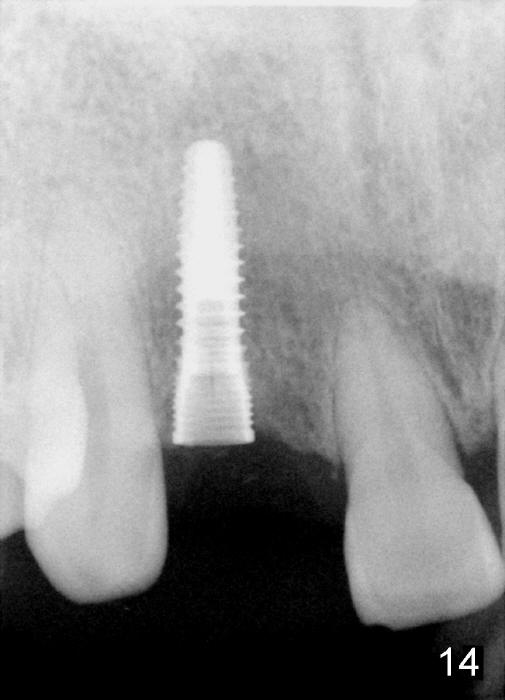

Preop PA shows that the edentulous space is extraordinarily wide mesiodistally (Fig.13 double arrows). There should be enough room to place osteotomy lateral to the implant (3.8x14 mm, Fig.14, immediately post placement).